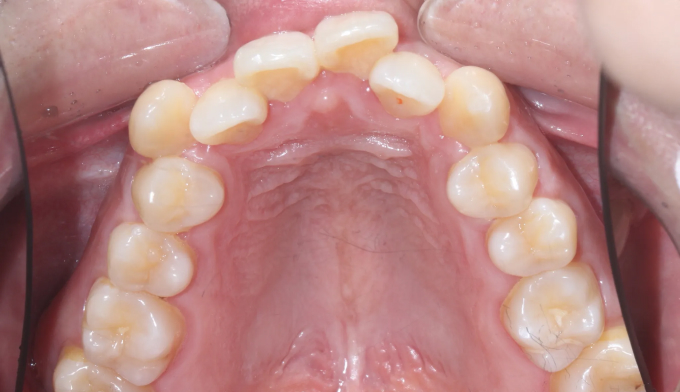

주걱턱과 돌출입, 그리고 덧니를 한꺼번에 가지고 있는 경우입니다. 이 모두를 해결하기 위해서는 필요한 공간의 양이 많기 때문에 성인에서는 작은어금니 발치가 대부분 필요합니다.

교정치료를 통해 치열이 고르게 된것은 물론, 주걱턱과 돌출입이 개선되면서 입술 모양이 보다 더 자연스러워지고 안모가 개선되었습니다.

총 교정치료는 21개월입니다.